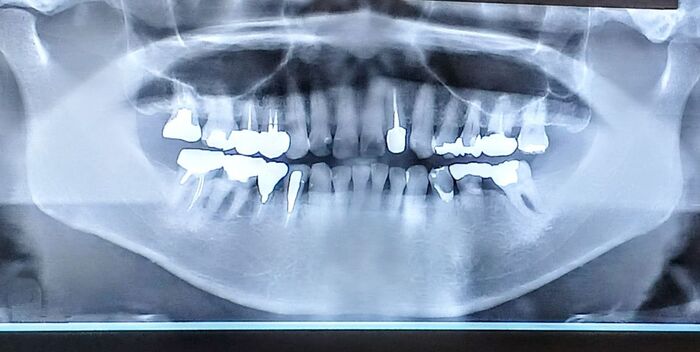

治療の最初のステップは、精密検査とカウンセリングです。口腔内の状態を確認するため、レントゲンやCTスキャンなどで顎骨の密度や健康状態を評価します。その後、治療計画を立てるために患者の希望や健康状態に基づいた詳細な説明が行われます。

インプラント治療は、まず詳細な診査と治療計画の立案から始まります。歯科医師は患者の口腔内の状態を確認し、CTスキャンやX線を用いて顎骨の厚みや高さを評価します。この情報を基に、インプラントの埋入位置を正確に決定します。